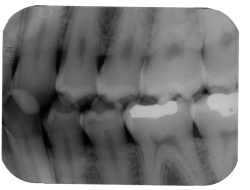

| A horizontal angulation error can produce an image with interproximal overlap. |

Use bitewings? Forced to place receptors diagonal to the teeth? Watch out for horizontal angulation errors, which produce a too-wide image with interproximal overlap. The solution is to shoot the x-rays through interproximal surfaces.